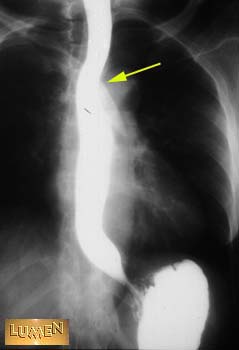

What causes the constriction?

Answer

Arch of the aorta.